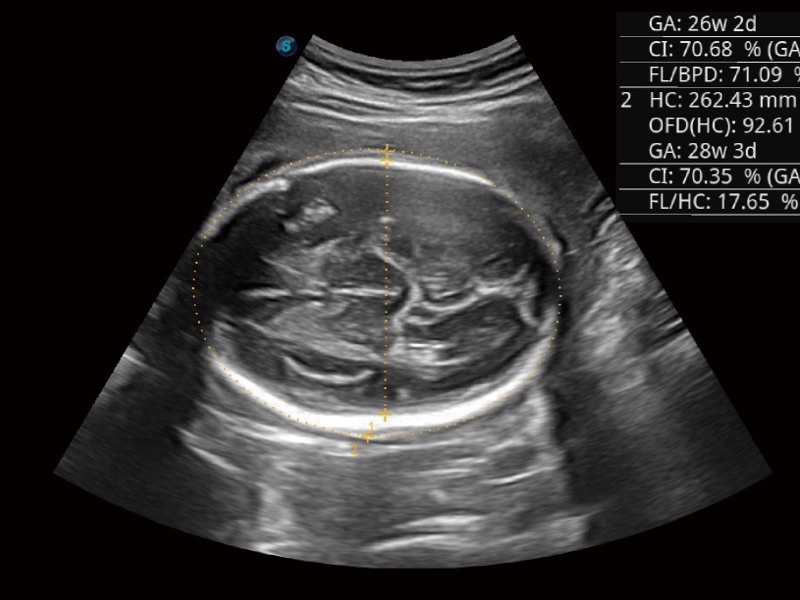

妇产科应用

超声检查得益于实时性、经济性、便捷性,目前广泛的应用于临床工作中,超声检查设备已成为帮助临床医生轻松地完成诊断工作的好伙伴。P20 Plus集成了一整套包含了腹部、心血管、小器官、妇产科等全面临床应用功能,轻松应对各种临床问题。